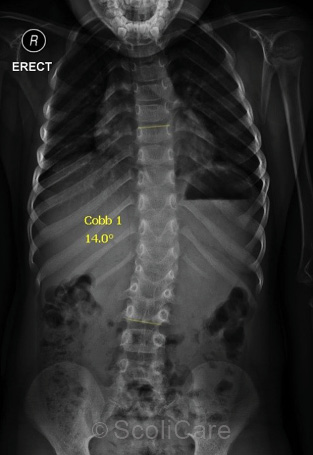

By the end of the bracing period, the patient’s scoliosis had been reduced from 40° down to 14° out of the brace (Figure 2).

Figure 2: Out of brace x-ray

The child wore the brace for 24 months which resulted in a reduction of the curve from 40° down to 14°. The child is still under care and will continue with a soft-brace to encourage the correction of the remaining deformity as the child grows.